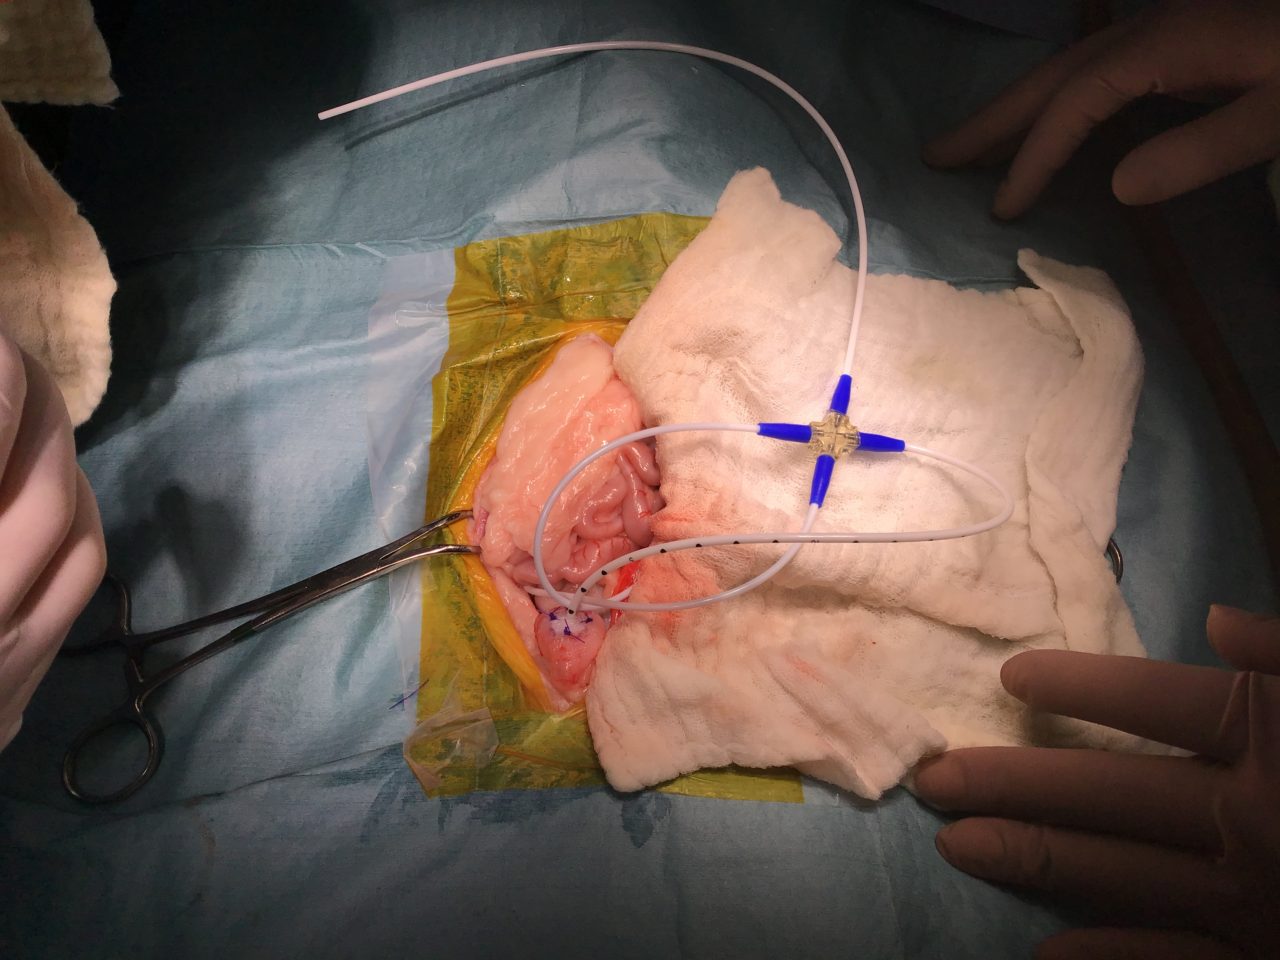

猫さんが急に具合が悪くなって、かかりつけ医を受診したところ血液検査で腎数値が著しく上昇し、高カリウム血症になっているとのこと。すぐに原因を調べて必要な処置をして欲しいとのことで来院されました。無麻酔CTでは尿管結石は確認されませんでした。すぐに拡張した腎盂に腎瘻カテーテルを設置し、尿の排泄路を確保しました。数日後アシドーシス、高カリウム血症は改善されました。尿管炎に伴う尿管の運動機能障害、エックス線に映らない結石の閉塞(99%近くシュウ酸Caなのでまず考えにくい)などが考えられましたが、腎瘻カテーテルを一時的に閉鎖すると腎数値が上昇傾向にあるため、両側の尿管の機能障害と判断しSUBシステム(人工尿管)によるサルベージを行いました。手術の翌日には腎数値は正常に回復しました。CTによる猫の尿管結石の検出感度は非常に高く、術式の決定や治療方針について細かい評価が可能です。今後は血液検査で腎数値のモニタリングを行いながら、定期的にインプラントの洗浄やメンテナンスが必要になります。